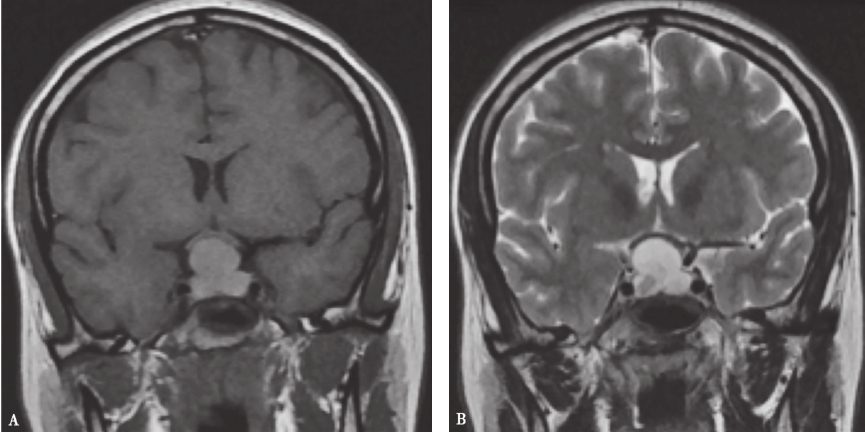

图1Rathke囊肿的MRI表现

鞍区及鞍上囊性占位,以中线大致对称分布,T1及T2WI 呈高信号,壁菲薄,囊内见T2WI 低信号结节影,增强后呈薄壁环形强化,不完整,囊内结节无明显强化;A.冠状位T1WI;B.冠状位T2WI;C.增强冠状位T1WI;D.矢状位T1WI;E.增强矢状位T1WI